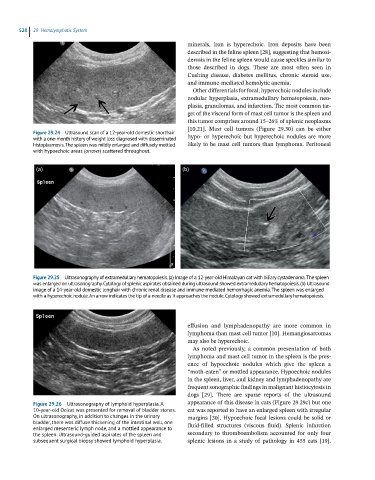

Figure 29.25 Ultrasonography of extramedullary hematopoiesis. (a) Image of a 12-year-old Himalayan cat with biliary cystadenoma. The spleen

was enlarged on ultrasonography. Cytology of splenic aspirates obtained during ultrasound showed extramedullary hematopoiesis. (b) Ultrasound

image of a 14-year-old domestic longhair with chronic renal disease and immune-mediated hemorrhagic anemia. The spleen was enlarged

with a hyperechoic nodule. An arrow indicates the tip of a needle as it approaches the nodule. Cytology showed extramedullary hematopoiesis.